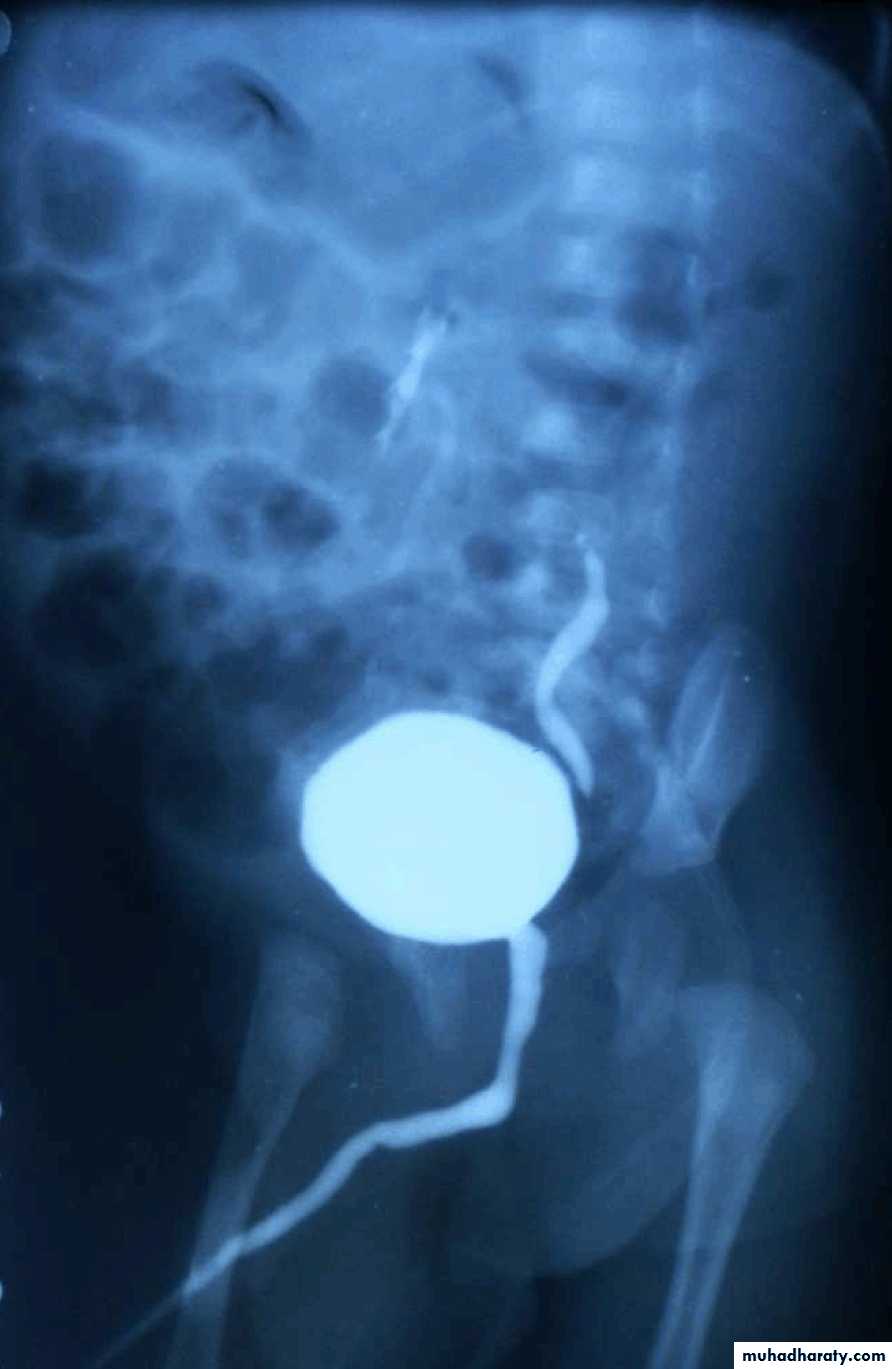

Micturating Cystourethrography (MCUG)

VUR is classified into 5 grades depending on the severity of reflux and the associated dilatation of the renal system.